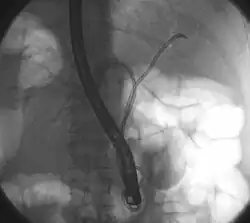

Das zuerst durchgeführte bildgebende Verfahren ist in der Regel die Ultraschalluntersuchung des Bauches. Sie eignet sich vor allem zur Erkennung gutartiger Ursachen der Symptome (wie z. B. Gallensteine) und zur Darstellung erweiterter Gallenwege bei der Cholestase. Auch Tumoren bzw. Metastasen im Lebergewebe sind im Ultraschall häufig zu erkennen. Der Klatskintumor kann unter Umständen so erkannt werden. Generell eignet sich Ultraschall aber nicht zur sicheren Darstellung des Tumors und zur Ausbreitungsbestimmung. Die Untersuchung der Wahl dafür ist die Computertomographie (CT) mit Kontrastmittel von Brustkorb und Bauch. Hier kann die Lage und Ausbreitung des Tumors bestimmt werden und dazu, ob bereits Lymphknoten befallen sind und ob der Tumor benachbarte Blutgefäße wie die Pfortader ummauert oder in sie einwächst. Zur Planung der Operation können hier auch die Lebergefäße dargestellt und die Größe der Lebersegmente und das verbleibende Lebervolumen berechnet werden. Die Untersuchung ist ein wichtiger Teil der Stadienbestimmung. Ergänzend kann eine Magnetresonanztomographie (MRT) mit Kontrastmittel zur besseren Darstellung der Gallenwege und des Tumors durchgeführt werden. Die sonst bei Erkrankungen der Gallenwege häufig eingesetzte ERCP, eine invasive Methode zur Darstellung der Gallenwege mit der Möglichkeit zur Intervention, wird bei Verdacht auf Klatskintumoren zurückhaltend eingesetzt, da hier das Risiko für eine bakterielle Cholangitis deutlich erhöht ist. Alternativ bietet sich die nicht-invasive MRCP an. Die ERCP kommt vor allem bei unklaren Fällen zum Einsatz, um mit einer kleinen Bürste Zellen aus dem verdächtigen Gangabschnitt zu gewinnen (Biopsie). Diese können bei der Diagnose den Weg weisen. Die ERCP ermöglicht auch therapeutisch die Einlage von Stents zur Entlastung der Cholestase.[3][8][13]